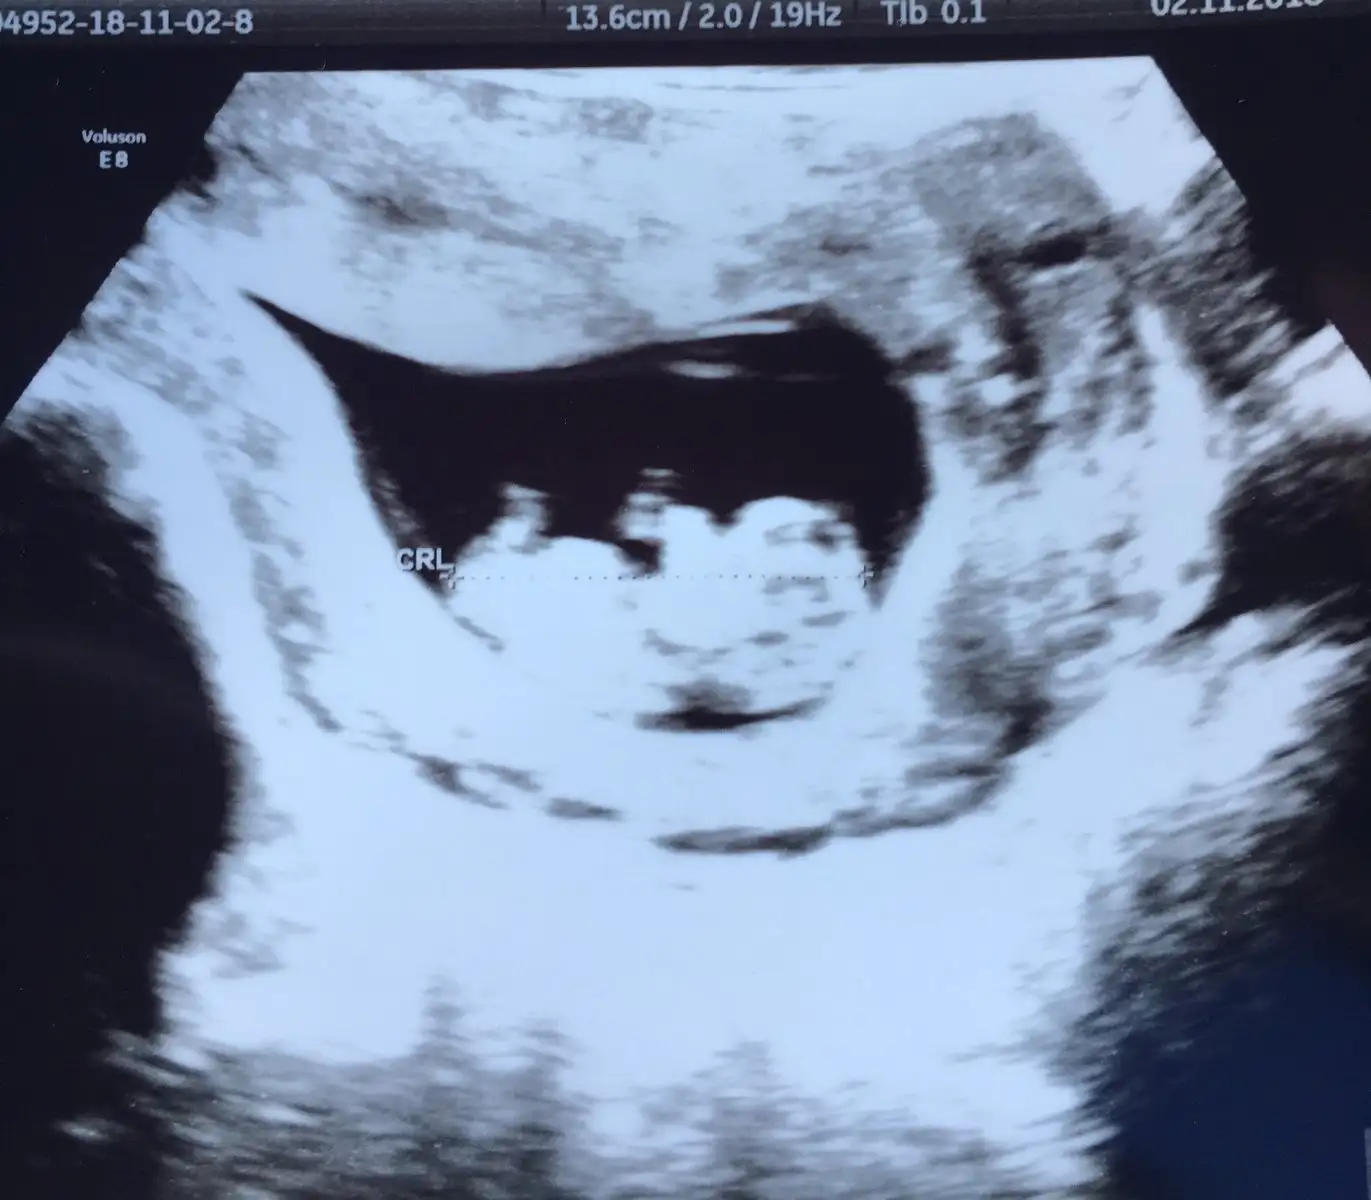

Yaaa cok tatli ama buuuBuraya taşınmışsınız canlarHemen ultrason fotosunu atıyorum size teyzeleri :) Zeytintanem yorgun anneanne BirTutamMutluluk20 Kmsl Hnd

Değil canımm 10 haftalığız daha :) Ne hissettin peki cinsiyet hakkında :)Yaaa cok tatli ama buuutipki anasi bu arada cinsiyeti belli mi canim?

maşallah Rabbim kucağın almayı nasip etsinBuraya taşınmışsınız canlarHemen ultrason fotosunu atıyorum size teyzeleri :) Zeytintanem yorgun anneanne BirTutamMutluluk20 Kmsl Hnd